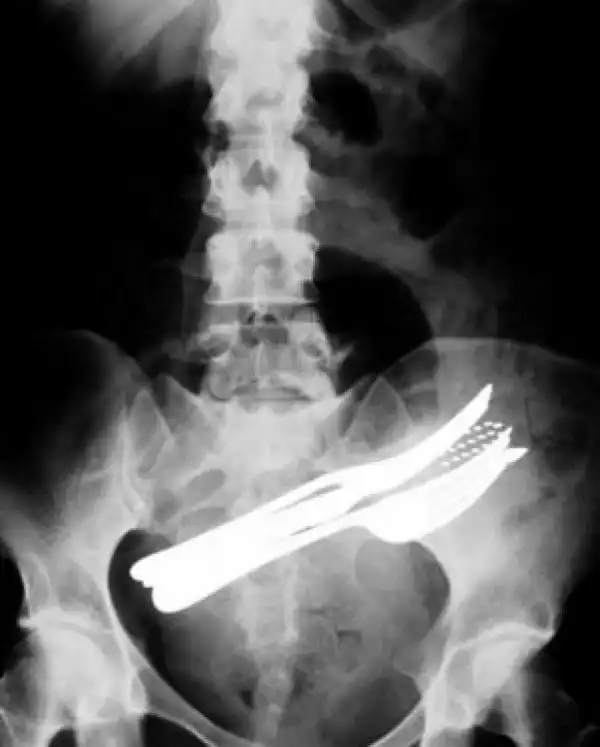

Врачебные находки в интимных местах

Или как впихнуть невпихуемое :lol: